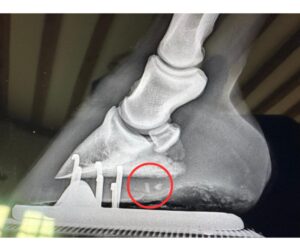

Radiography is also used frequently during surgical procedures, such as fracture repair, and a digital x-ray system in theatre permits instant imaging to help optimise these procedures.